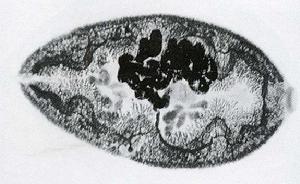

是人體並殖病主要病原。衛氏並殖吸蟲成蟲蟲體肥厚,背側稍隆起,腹面扁平。活體紅褐色,不停做伸縮運動,體型不斷變化,固定後染色蟲體在光鏡下可見體表面布滿小棘,大多為單生型。口、腹吸盤大小略同,腹吸盤約在蟲體中部。卵巢與子宮並列於腹吸盤之後,卵巢6葉,兩個睪丸分支如指狀,並列於蟲體後1/3處。卵巢類型、口、腹吸盤比例、睪丸長度比是並殖吸蟲形態鑑別重要特徵。蟲卵呈橢圓形,卵蓋大且常略傾斜。

並殖吸蟲病形態:衛氏並殖吸蟲成蟲蟲體肥厚,背側稍隆起,腹面扁平。活體紅褐色,不停做伸縮運動,體型不斷變化,固定後染色蟲體在光鏡下可見體便布滿小棘,大多為單生型,偶爾可見簇生及混生者。口、腹吸盤大小略同,腹吸盤約在蟲體中部。消化器官包括口、咽、食管及兩支彎彎曲的腸道。卵巢與子宮並列於腹吸盤之後,卵巢6葉兩個睪丸分支如指狀,並列於蟲體後1/3處。卵巢類型、口、腹吸盤比例、睪丸長度比並殖吸蟲形態鑑別重要特徵。蟲卵呈橢圓形,卵蓋大且常略傾斜。